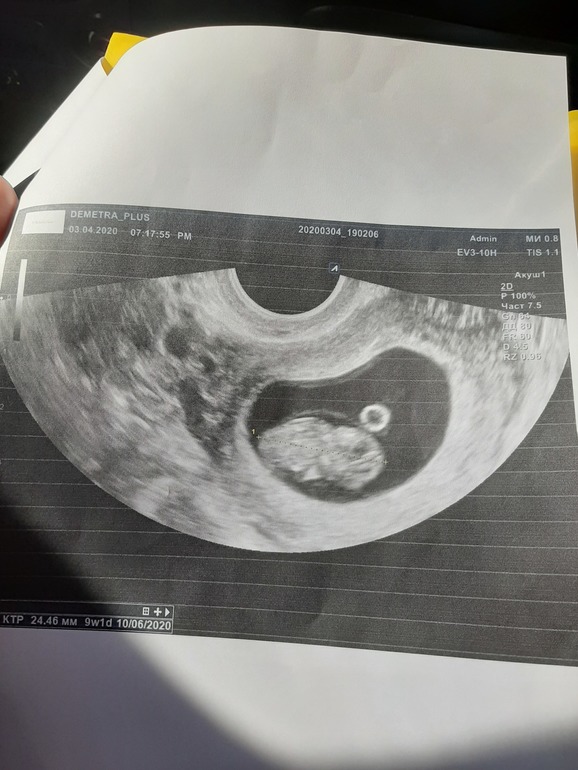

9 недель

В общем, не буду томить, у нас все хорошо, сердечко бьется, эмбрион шевелится. По ктр даже опережает срок на 1 день))

Плодное яйцо 72*35 мм, КТР 24.5 мм. 2 с половиной см уже человек))